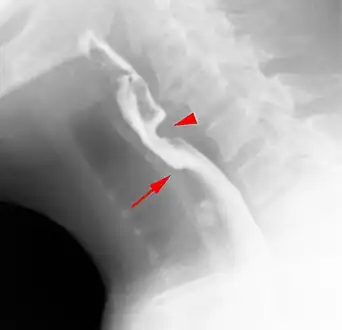

Esophageal web stenosis in barium swallow examination lateral view.

Web with "jet-phenomenon". Arrowhead on incomplete opening of the upper esophageal sphincter.

The diagnostic test of choice is a barium swallow.